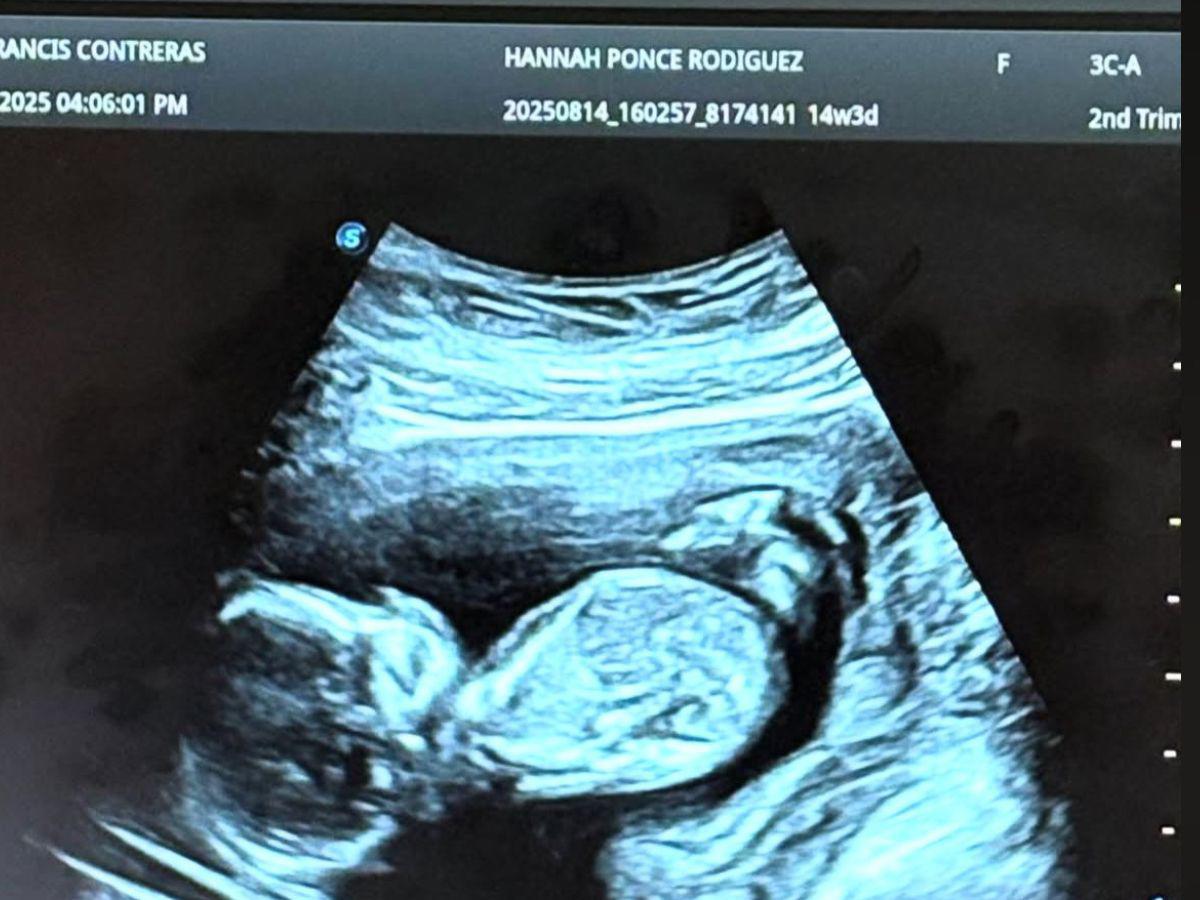

Fotografía de la ecografía del embarazo de Hannah en redes sociales. "Papá y mamá te esperan con ansias mi princesa, ya nos tienes loquitos de amor", publicaron en ese entonces los esposos.